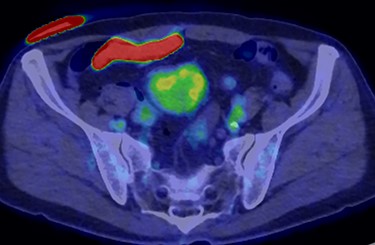

A 70-year-old man underwent robot-assisted laparoscopic cystectomy with bladder replacement for bladder cancer. The pathological diagnosis was stage 0 (Tis, N0, M0). Nine months after the operation, no plain computed tomography (CT) findings indicated cancer recurrence. Thirteen months after the operation, contrast-enhanced CT showed a well-defined intra-abdominal mass, up to 50 × 40 mm in size, with heterogeneous enhancement. The tumor was in contact with the small intestine (Fig. 1). Magnetic resonance imaging (MRI) revealed an isolated mass with hypointensity on T1-weighted images and mild hyperintensity on T2-weighted images (Fig. 2a and b). Fluorine-18 fluorodeoxyglucose positron emission tomography CT (FDG-PET/CT) revealed mild FDG uptake in the tumor, with a maximum standardized uptake value (SUV max) of 3.4 (Fig. 3). Based on these findings, bladder cancer recurrence or mesenchymal tumors derived from the small intestine or mesentery were suspected. The tumor showed a rapid growth trend and required immediate therapeutic intervention. However, a differential diagnosis based on the imaging findings alone was difficult to achieve. Therefore, we decided to perform a diagnostic surgery to identify the intra-abdominal tumor.

FDG-PET-CT showed FDG uptake in the tumor, with a SUVmax of 3.4.